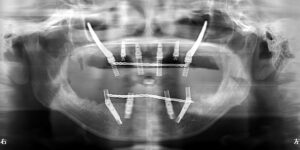

手術後パノラマX線写真

下顎オールオンフォー、上顎ザイゴマインプラント

日帰り全身麻酔により、上下顎同時に手術。

治療期間

6ヶ月